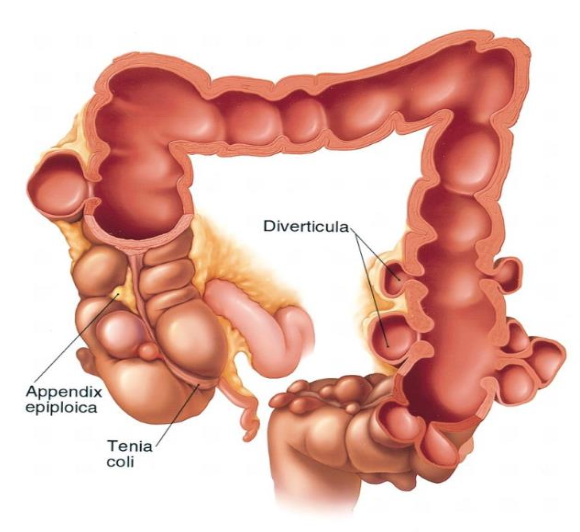

Diverticulosis:

- Small pouches due to herniation of the mucosa into colonic wall

- False diverticula